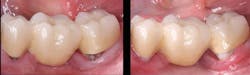

If the caries lesion appears to be deeply involved under the crown, accomplish the following crown technique. If not, conservatively remove the caries until sound tooth is found and restore the area with a cariostatic material, such as resin-modified glass ionomer or conventional glass ionomer (figure 1).

Figure 1: Fixed partial denture placed several years previously and repaired with 3M Ketac Nano resin-modified glass ionomer. This technique is commonly used, but it is seldom esthetically pleasing or long-lasting.